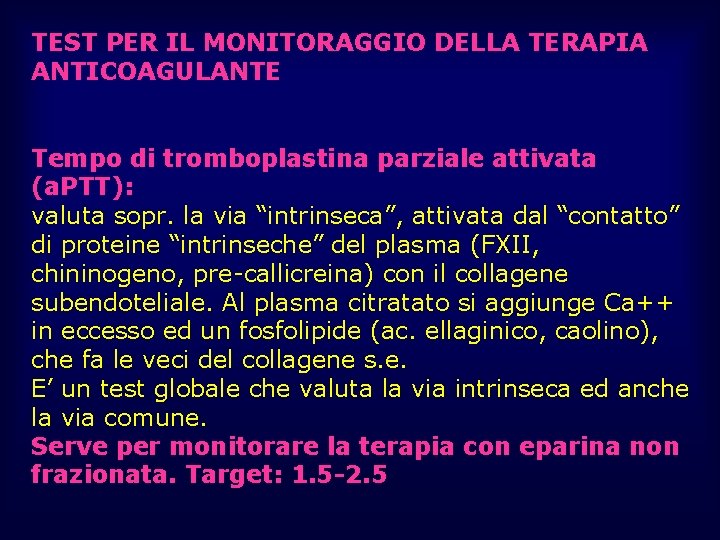

TEST PER IL MONITORAGGIO DELLA TERAPIA ANTICOAGULANTE Tempo di tromboplastina parziale attivata (a. PTT): valuta sopr. la via “intrinseca”, attivata dal “contatto” di proteine “intrinseche” del plasma (FXII, chininogeno, pre-callicreina) con il collagene subendoteliale. Al plasma citratato si aggiunge Ca++ in eccesso ed un fosfolipide (ac. ellaginico, caolino), che fa le veci del collagene s. e. E’ un test globale che valuta la via intrinseca ed anche la via comune. Serve per monitorare la terapia con eparina non frazionata. Target: 1. 5 -2. 5